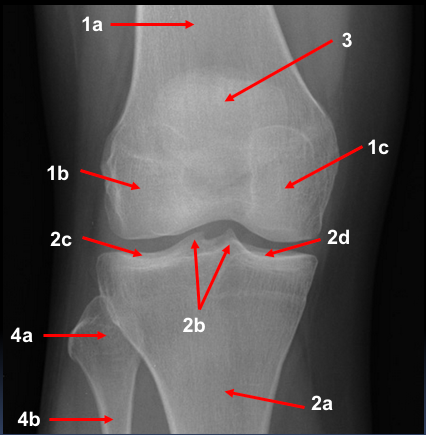

A 70 year old woman presented to her GP with a long history of pain in her left knee that was becoming worse and limiting her movement.

On examination the patient had a good range of movement, but there was some discomfort in her left knee on movement and crepitus (crunchy noise and feeling when moving joint).

This 75 year old woman presented with difficulty walking and knee pain. How would you describe these X-rays?